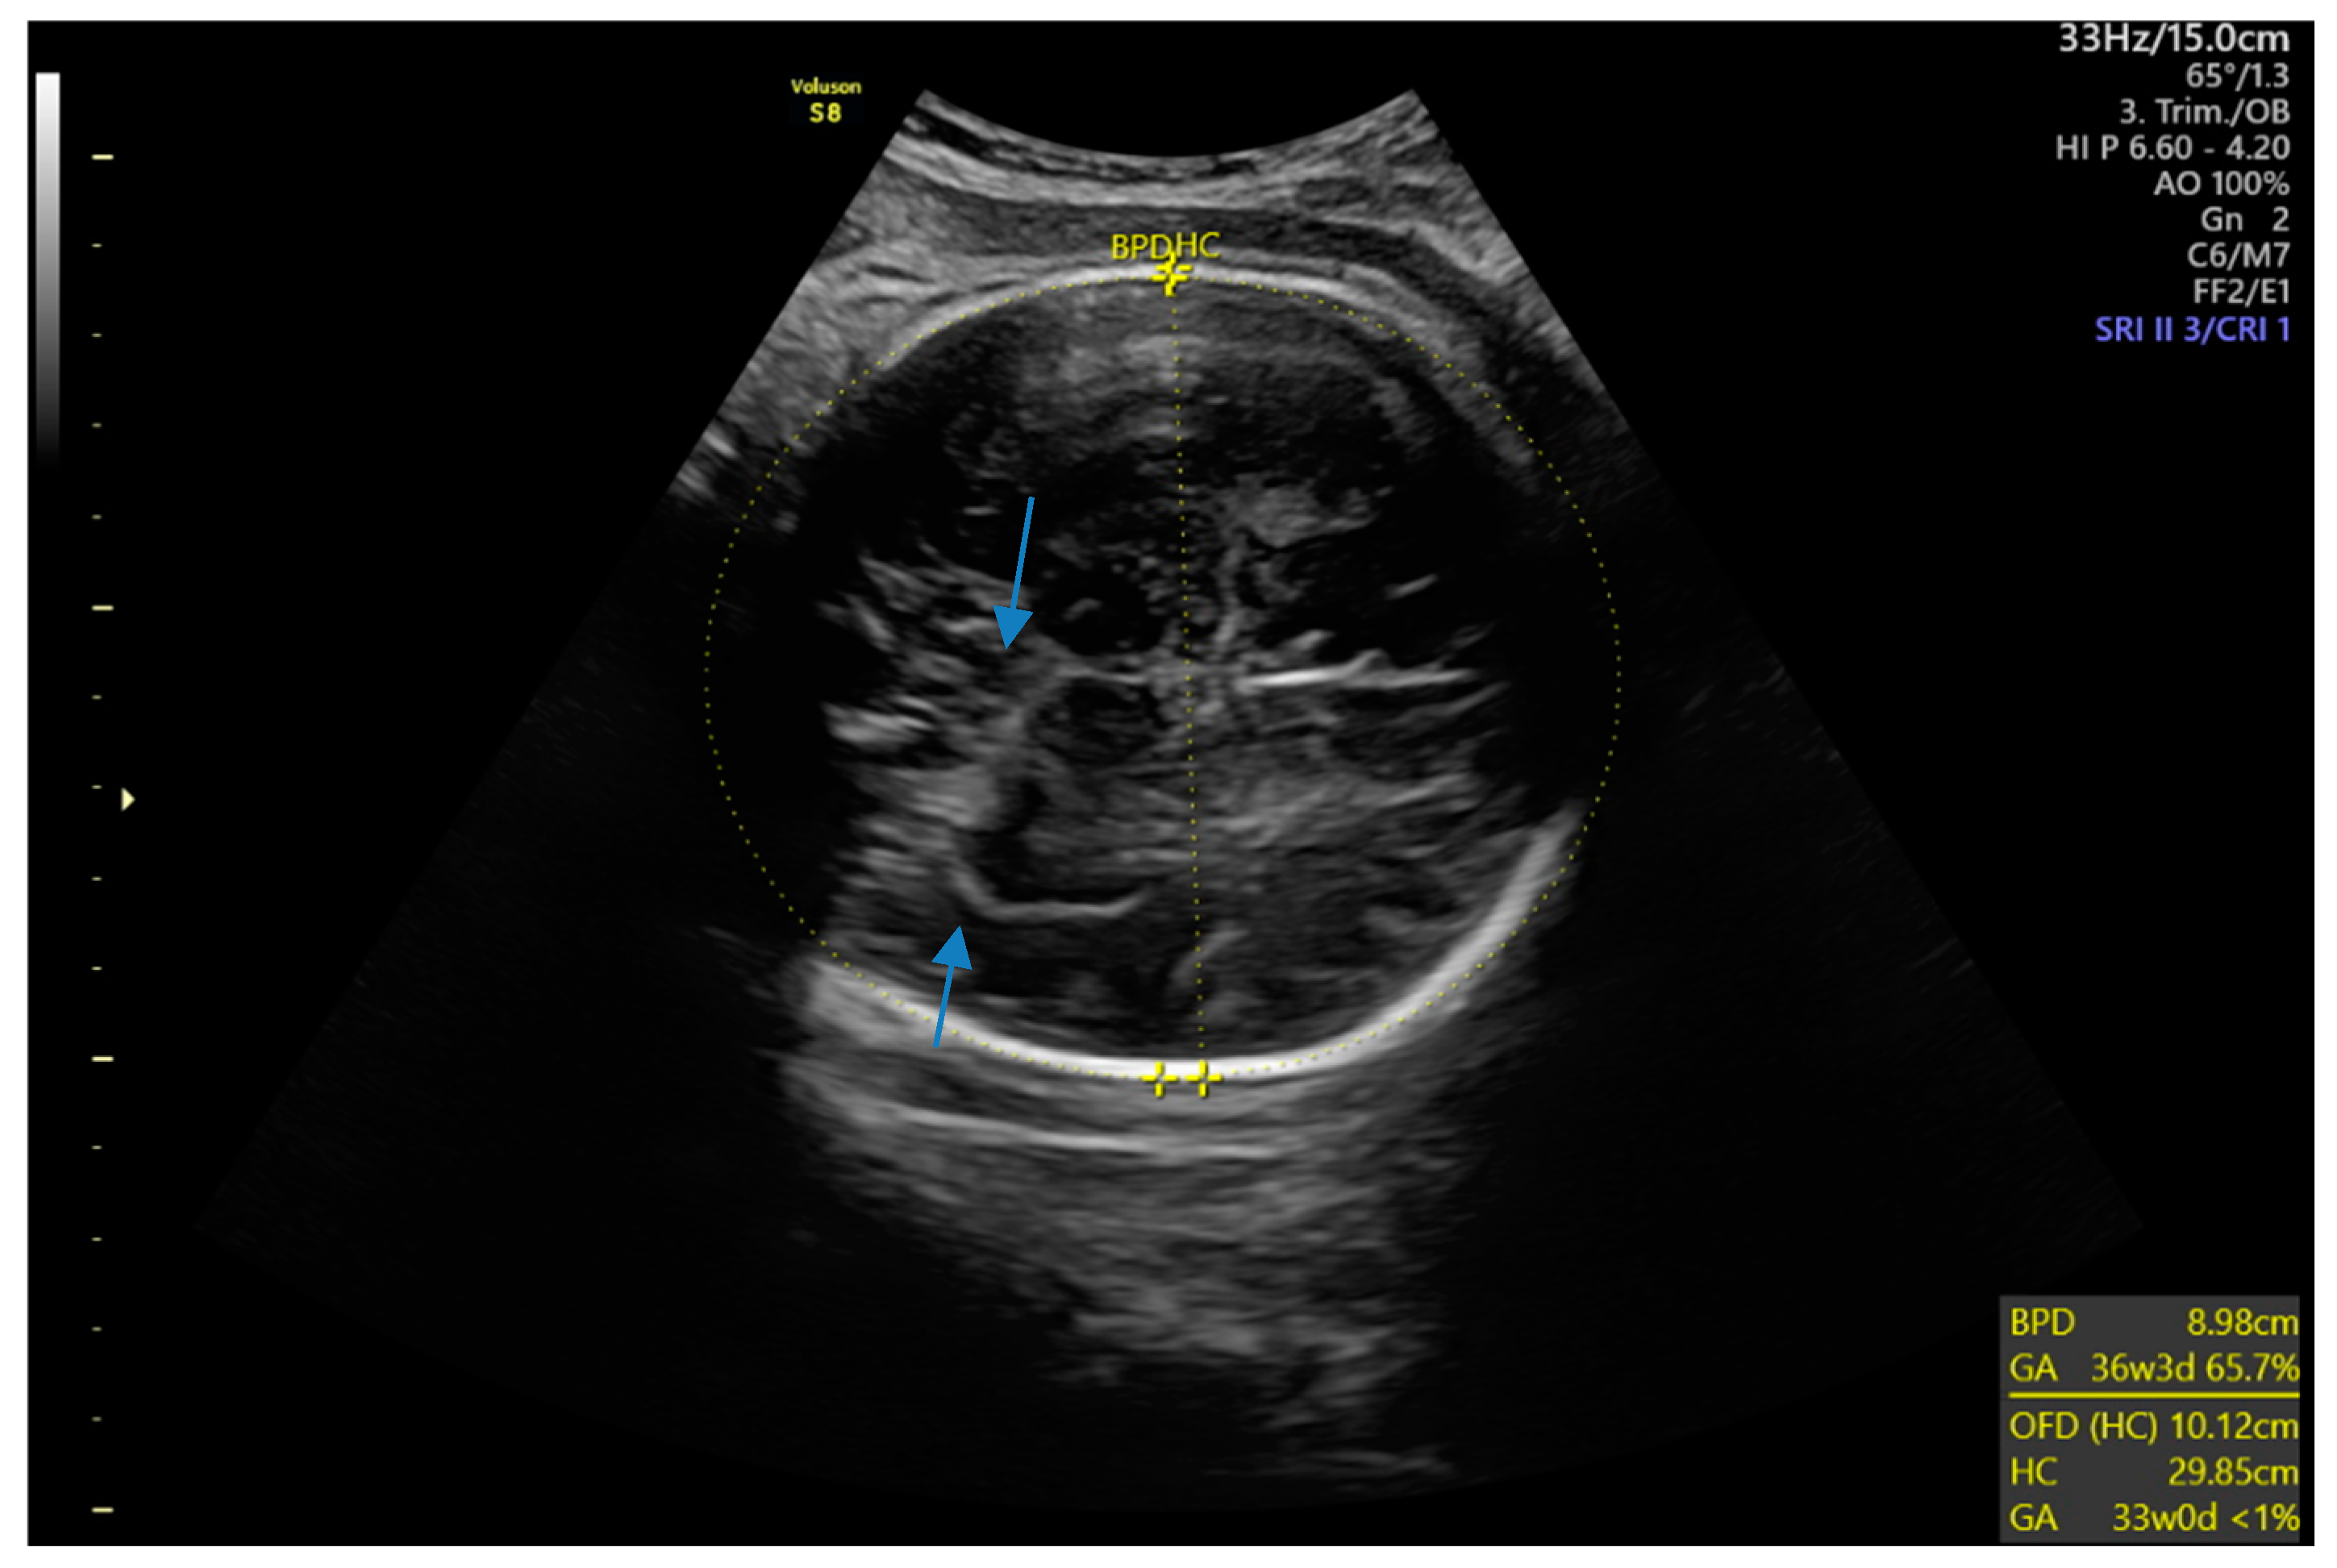

Six months later, a second ultrasound scan and a consecutive MRI scan to follow-up and control the success of the therapy were performed. The ultrasound revealed a decrease in the size of the cyst from 10 cm in maximal diameter to 9 cm and showed multiple circular septations, indicating an involuting cyst (Figure 7). In contrast to the preceding MRI scan, typical T2 hypointense membrane-like structures were observed within the lesion in T2WI. These represented most probably the floating membranes, the typical water-lily sign (Figure 8). T1WI (Figure 9) showed the cyst as a hypointense lesion, but the membranes could only be clearly observed in T2WI. Consecutively, the cyst was classified as WHO-CE3A.

Figure 7.

Second ultrasound scan: The right lobe of the liver reveals a round, fluid-filled cystic lesion with several septations (arrows), indicating the degenerating cystic wall of a stage-CE3a hydatid cyst.

The most important differential diagnosis for CE is a cyst with calcification [2]. Ultrasound depicts calcification and is often used as a screening tool because it is not only highly sensitive and specific, but also a non-invasive, widely available, and cost-efficient mode of investigation [2,13]. The cyst wall typically appears as two echogenic lines with a hypoechogenic fluid layer in between. Simple cysts lack internal structures, but a hydatid cyst may show echogenic foci, known as hydatid sand, that shift to the lowest part of the cyst when the patient is repositioned. This movement creates a snowstorm sign, where the foci appear scattered, like a snowstorm, without forming distinct layers [7], as observed in our case. A water-lily sign on an ultrasound, CT, and MRI scan is used for describing the detachment of the membrane inside of the cyst. Depending on the membrane configuration, it can also be observed as a snake sign (also called serpent sign) [14].